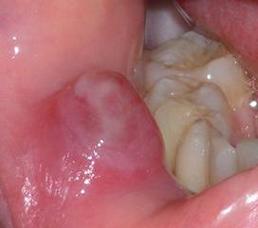

口腔粘液腺囊肿自愈吗

这是一个非常常见的问题,关于口腔粘液腺囊肿是否会自愈,答案是:有自愈的可能,但概率不高,并且不推荐等待自愈。

首先要了解它的成因,口腔粘液腺囊肿通常是由于唾液腺导管(小管道)被堵塞或破裂,导致分泌的粘液无法正常排出,积聚在腺体或周围组织中形成的。